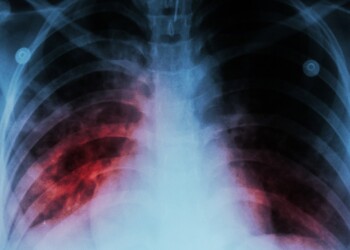

Read moreLa tuberculosis, una enfermedad bacteriana que afecta principalmente los pulmones y se transmite por vía aérea, mostró un crecimiento sostenido ...

Read moreLa tuberculosis (TB) es una de las enfermedades más antiguas que afectan a la humanidad. A pesar de los avances ...